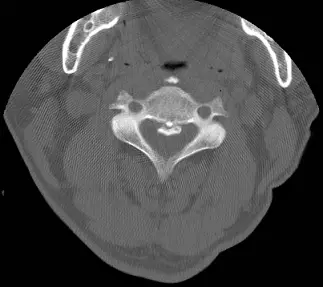

60 歲男性病患因長期頸部疼痛接受電腦斷層檢查,發現第 3 至第 4 頸椎有一鈣化病灶如圖。其診斷為何?

- 椎體後方見弧狀或板狀高密度構造,位於硬脊膜前方,即PLL位置,造成脊髓管輕度狹窄。

- 無骨膜反應、無椎體破壞、無髓腔內空洞或脊椎旁軟組織腫塊。

上述影像特徵符合「韌帶內形成骨化或鈣化」而非椎體骨折缺損或軟組織感染破壞。